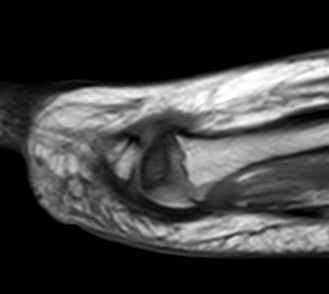

MRI